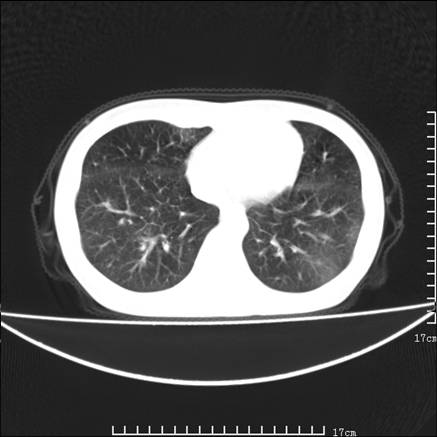

女,46岁,患胃溃疡多年,溃疡大小约1.0cm左右,后于5年前手术,病理为胃癌。主诉:半月前感冒后胸闷,气短,有咳嗽,无明显咳痰,无发热。偶有腰背部不适。

以下为高分辨扫描图像

双肺小叶间增厚,双肺散布粟米影和磨玻璃状影,以双肺上叶为重。结合病史考虑转移(癌性淋巴细管炎)可能性大。

究竟是不是癌性淋巴管炎,抗炎治疗后复查就会明了,抗炎治疗癌性淋巴管炎是不会改善的.个人感觉叶间裂虽然增厚,但比较光滑,符合炎性改变!

支持 肺间质性肺炎,不除外癌性淋巴管炎,建议抗炎治疗复查---------小叶间隔增厚,磨玻璃影及片絮状影